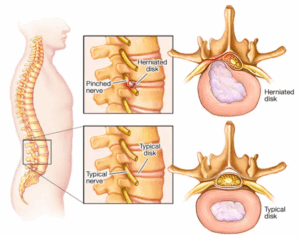

Pinched nerve

A pinched nerve occurs when too much pressure is applied to a nerve by surrounding tissues, such as bones, cartilage, muscles or tendons. This pressure can cause pain, tingling, numbness or weakness.